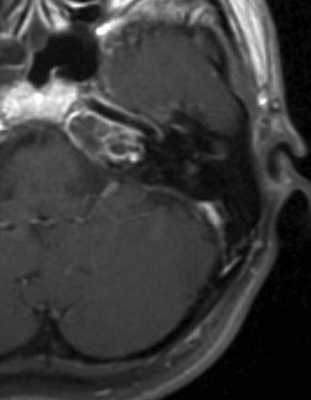

МРТ головного мозга. Аксиальная Т2-взвешенная МРТ. Правосторонний мастоидит (стрелка).

МРТ головного мозга. Корональная Т1-взвешенная МРТ с контрастированием. Мастоидит с поднадкостничным абсцессом.

МРТ головного мозга. Корональная Т1-взвешенная МРТ с контрастированием. Мастоидит.

МРТ головного мозга. МР-венография. Мастоидит с тромбозом поперечного синуса.

МРТ головного мозга. Аксиальная Т1-взвешенная МРТ с контрастированием. Апицит.